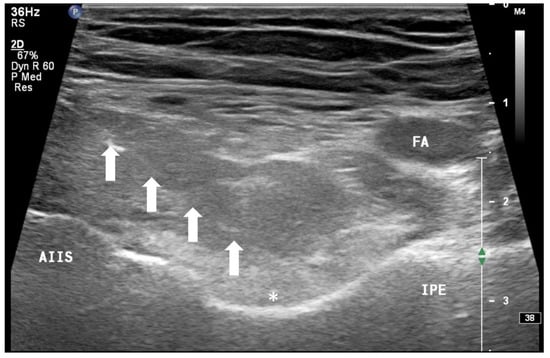

In addition to the classical PENG injection, our modified approach highlighted the addition of pericapsular infiltration in the iliopsoas plane to cover the low articular branch of the femoral nerve and a sagittal approach to target the ONAB. The algorithm was still used to perform diagnostic blocks, followed by alcohol neurolysis 10 min later for those with a positive diagnostic block in the same setting under real-time ultrasound guidance (Philips Affiniti 70, 5–12 MHz linear probe or 1–5 Hz curved probe depending on the depth of the target). In the modified approach, the procedure consisted of 3 needle insertions with the use of 22-gauge 10 cm Quincke needles. The first needle for the high femoral nerve articular branches (high FNAB branches) and AON was inserted in the same way as the PENG approach between the anterior inferior iliac spine (AIIS) and the iliopubic eminence (IPE) deep to the psoas tendon (Figure 2 and Figure 3). A second needle for the low branches of FNAB was inserted in-plane from lateral to medial and advanced through the sartorius, rectus femoris and iliopsoas muscles. The final needle position was in the plane superficial to the iliofemoral ligament medial to the rectus femoris tendon over the femoral head (Figure 4 and Figure 5). The third injection for the obturator nerve articular branches was used to target the caudal aspect of the inferomedial acetabulum (IMA) by scanning in a sagittal plane with a caudal-to-cephalad needle trajectory. The precise localization of the caudal aspect of the IMA could be first approached via the ordinary way (an oblique scan) as described in our first case series [5]. The probe was slowly rotated obliquely until the acetabulum, femoral head, and neck were aligned in the same plane, with the superomedial acetabulum coming into view. The probe was then slid caudally with the end point being the presence of the acetabulum without the femoral head. This referred to the location of the inferomedial acetabulum. The probe was then adjusted until the IMA was in the middle of the image, followed by rotating the probe by approximately 60 degrees (Figure 6). In this scan, the pectineus, the caudal aspect of the IMA and, occasionally, the obturator externus were seen. The ONAB could be visualized in the wedge of the subpectineal space directly adjacent to the IMA. Before any needle insertion, the probe was tilted slightly medially towards the obturator foramen to look for the acetabular/posterior branch of the obturator vessels which are usually deeper than the ONAB. The needle was then inserted from caudal to cephalad in-plane until the needle tip reached the wedge space consisting of the ONAB (Figure 7). In case the wedge space could not be clearly visualized, the needle tip would then be advanced until touching the caudal bony surface of the IMA directly underneath the pectineus. Then, 0.5–1% ropivacaine (4, 3 and 2 mL, respectively) was injected into the above three landmarks. The needles were left in situ during the diagnostic test while their positions were reconfirmed by ultrasound before 100% alcohol was injected into the above targets with volumes in a 1:1 ratio between alcohol and local anaesthetics. A decrease of ≥50% in composite pain score on hip flexion at 45 degrees 10 min after the blocks signified a positive diagnostic block. As a post-neurolysis routine manner, stylets were reinserted before needle withdrawal.

Figure 3. Ultrasound image showing injection of FNAB and AON by infiltration of the drug between the IPE and AIIS from lateral to medial (PENG approach). FA: femoral artery, AIIS: anterior inferior iliac spine, IPE: iliopectineal eminence, *: absolute alcohol spreading underneath iliopsoas muscle above the ASIS-IPE bone surface, white arrow: needle.